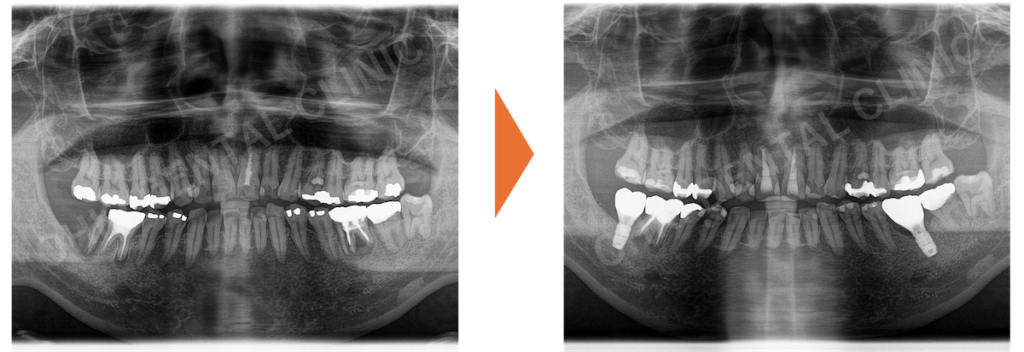

インプラント治療によって、重度の歯根破折を伴う欠損部位に噛み合わせを支える柱を再建し、残存歯の健康寿命を延ばした症例をご紹介します。

・パノラマレントゲン写真では、左下6番にも歯折と周辺の骨吸収が認められました。

Before / After の比較:

インプラントによって噛む機能と咬合支持が回復し、残存歯の負担軽減が期待できるとともに、天然歯に近いセラミック素材で欠損部を補うことで審美性も改善しました。

- インプラントを埋入したことにより、噛む機能が回復したことが大きな結果です。

- 噛み合わせの柱が再建されたことで、今後、残存している歯の破折リスクや負担が軽減されました。